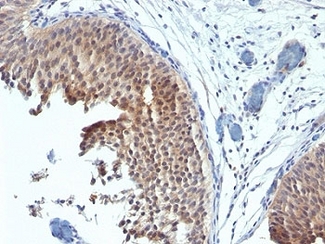

ERBB2 / HER2

Anti-ERBB2 / HER2 antibody IHC of human breast, carcinoma. Immunohistochemistry of formalin-fixed, paraffin-embedded tissue after heat-induced antigen retrieval. Antibody LS-B2133 concentration 5 ug/ml.